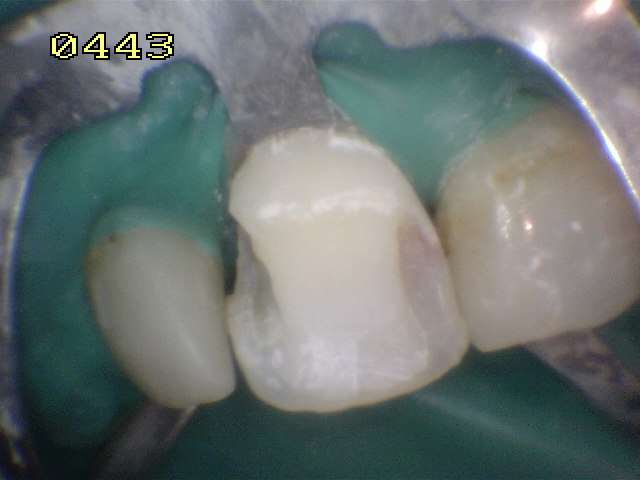

Aislación absoluta |

Microabrasión con acido